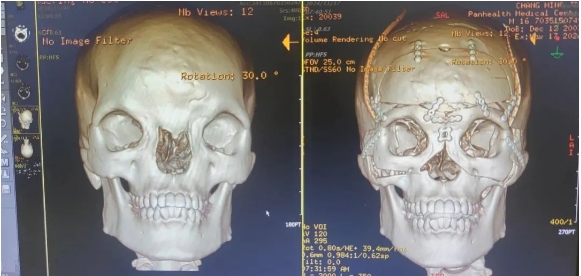

根據(jù)調(diào)查,正常男性的正常眶距平均為28mm,而初晨的雙眼內(nèi)眥角間距71mm,影像診斷報(bào)告顯示骨性眶間距55.69mm,兩側(cè)鼻骨低平、發(fā)育不良,已屬于最嚴(yán)重的Ⅲ度。

術(shù)前,整形外科劉斌團(tuán)隊(duì)聯(lián)合醫(yī)院影像中心,為初晨完善顱頜面部CT三維重建,進(jìn)行全面評(píng)估。為精準(zhǔn)的測(cè)量截骨量以防止術(shù)后復(fù)發(fā)和矯正不足,劉斌團(tuán)隊(duì)選擇利用計(jì)算機(jī)輔助技術(shù)模擬多次切割,來(lái)設(shè)計(jì)精準(zhǔn)的截骨線,從而避免可能出現(xiàn)的遠(yuǎn)期并發(fā)癥,并達(dá)到確切的美學(xué)效果。

手術(shù)非常順利,術(shù)后CT影像診斷報(bào)告顯示(如下圖),手術(shù)效果非常好,初晨?jī)裳酃切跃嚯x縮短至27mm,已在正常男性眼距范圍內(nèi)。